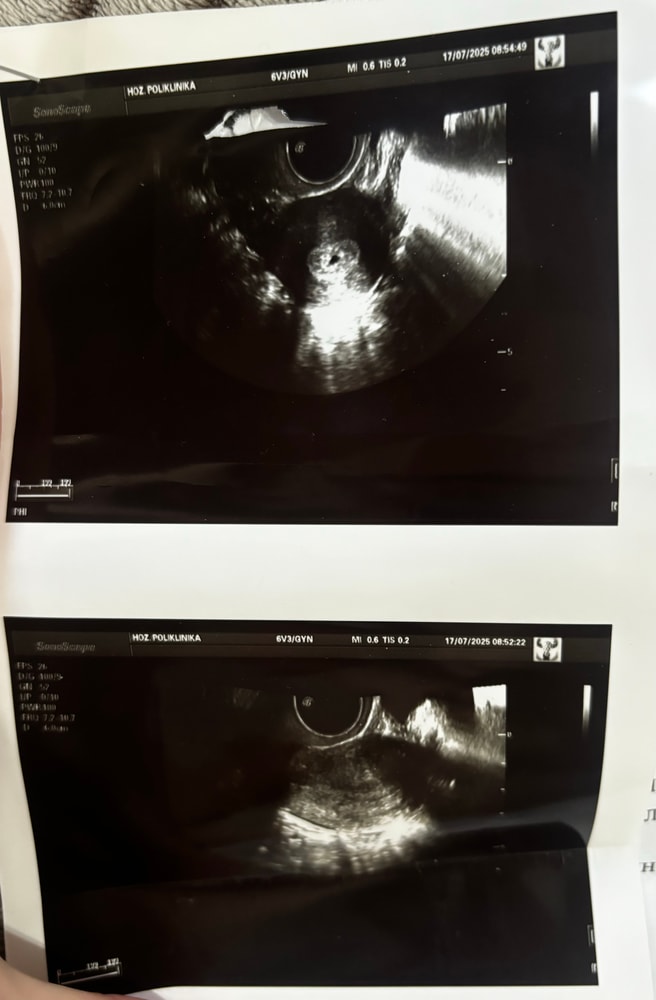

Медицинские вопросыВсем доброго дня! Второй день на измене ничего не понимаю. Постараюсь коротко и по делу. 17.06 была последняя менструация. 11.07 хгч был 264, 15.07 был 1526. 16.07 непонятные коричневатые выделения, испугалась и 17.07 пошла на УЗИ. Посмотрели трансвагинально на словах поняла, что плодное яйцо если это оно, еще не закрепилось в матке, но где именно оно тогда находилось я не поняла (приложу результаты узи, может есть те кто в теме, это была моя первая беременность я вообще ничего не понимаю🥲) после на кресле меня посмотрела гинеколог, взяла мазки и сказала что по мазкам нет конкретных примесей крови, ничего такого не назначила и отправила домой. Так же обнаружилась эрозия. Я приехала домой и через пару часов заметила, что у меня начала идти кровь, в перемешку с сгустками. Я поехала обратно, она меня посмотрела и выписала дюфастон по схеме каждые 8 часов. Сегодня утром 18.07 сдала срочный хгч он снизился до 1354, доктор сказал не пить больше таблетки и ждать. Я так понимаю, самый удачный исход- что все выйдет самостоятельно, самый не удачный- внематочная беременность. Как теперь эти два дня не сойти с ума я не знаю. Предполагаю, что удачного стечения обстоятельств где малыш смог зацепиться и остаться в самой матке - просто напросто нет. Теперь молюсь лишь бы не внематочная беременность. Посмотрите пожалуйста 🙏🏼 может кто разберется по узи все ли я правильно поняла??